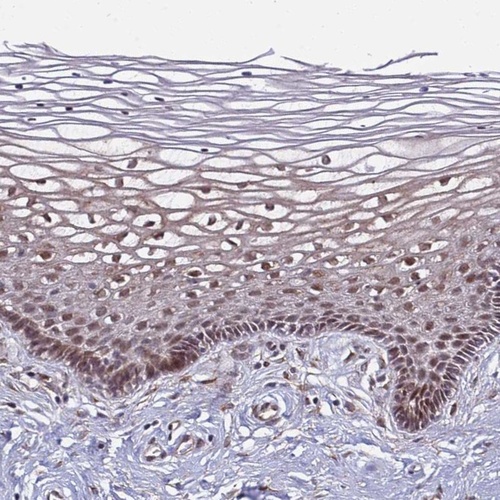

Immunohistochemical staining of human cervix, uterine shows nuclear positivity in squamous epithelial cells.